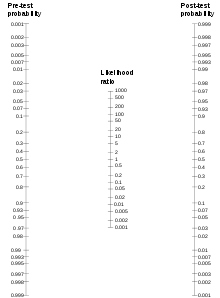

The relation can also be estimated by a so-called Fagan nomogram (shown at right) by making a straight line from the point of the given pre-test probability to the given likelihood ratio in their scales, which, in turn, estimates the post-test probability at the point where that straight line crosses its scale.

The post-test probability can, in turn, be used as pre-test probability for additional tests if it continues to be calculated in the same manner.[2]